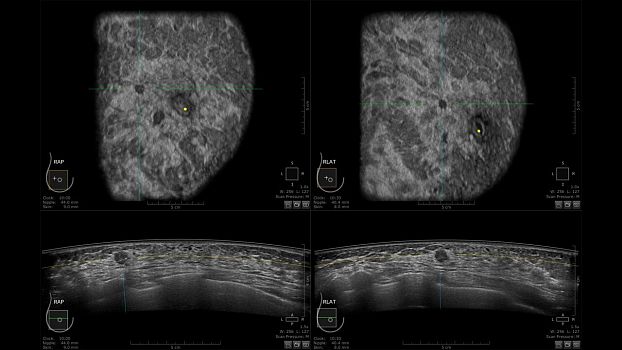

Клинические изображения

• Отображение объемных 3D ультразвуковых изображений, которые состоят из традиционных поперечных и воссозданных коронарных и сагиттальных проекций

• Стандартизованная ориентация изображения:

• Одновременный просмотр двух изображений для сопоставления в коронарной плоскости